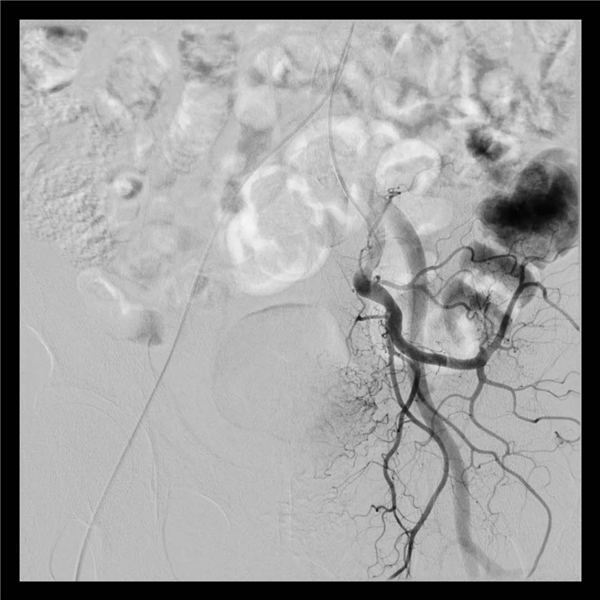

套上厚重的铅衣,站在明亮的无影灯下,两位主任开始了紧张而又有条不紊的介入手术。将一根1毫米粗的穿刺针穿刺入股动脉后,依次送入血管鞘、导丝、导管,再通过导管造影,膀胱癌就原形毕露了,肿瘤的供血动脉也清晰可见。

在透视镜的辅助下,将一根更细的微导管送入到肿瘤的供血动脉后,通过微导管将血管栓塞剂注入肿瘤供血动脉,再次造影,显示:膀胱癌的肿瘤染色已经完全消失不见。

这也就意味着膀胱癌的供血基本没有了,尿血症状也就能够得到控制。